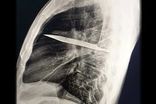

معلولیت خود خواسته برای گرفتن سهمیه پزشکی!